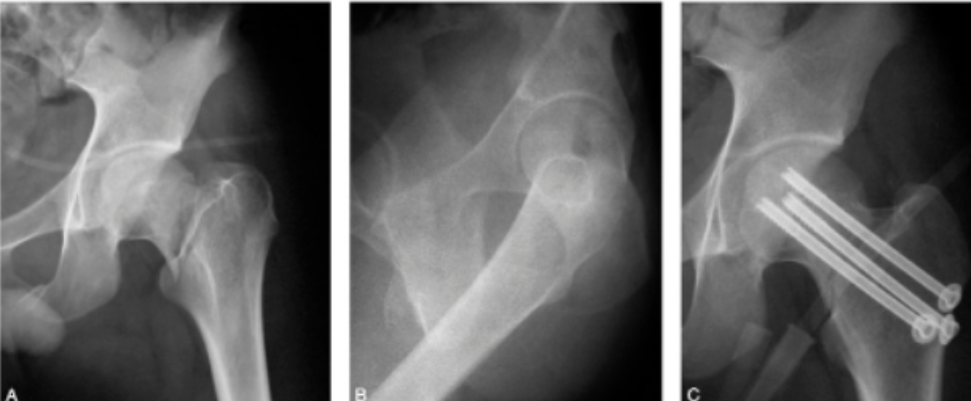

股骨近端骨折是老龄患者最常见的骨折之一,其中50%累及转子周围区域。老龄患者骨质疏松,PFNA内固定术后早期功能锻炼可能导致螺钉切割、内固定失效等并发症,而早期功能锻炼对患者功能恢复至关重要。因此,有学者研究了骨水泥加强的PFNA,以评估能否增加老龄患者患肢早期的负重能力。